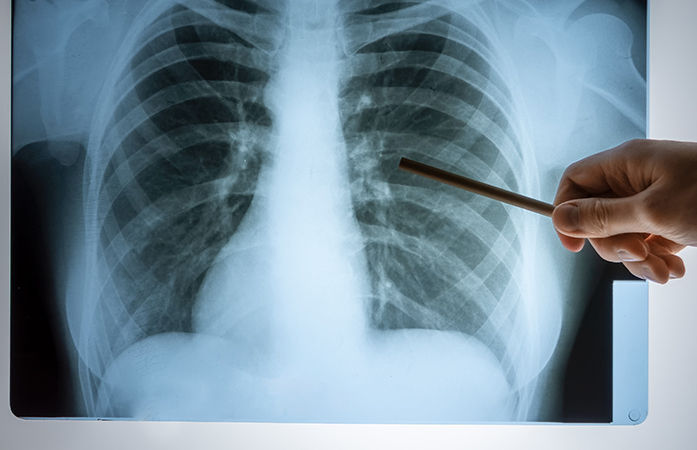

दरम्यान, Ahmedabad Municipal Corporation कडून TB नियंत्रणासाठी उपाययोजना सुरू आहेत. महानगरपालिकेच्या आरोग्य केंद्रांमध्ये मोफत तपासणी सुविधा उपलब्ध करून देण्यात आली असून स्पुटम टेस्ट आणि एक्स-रेच्या माध्यमातून निदान केलं जात आहे. वर्षभरात 1 लाख 49 हजार 710 संशयितांची तपासणी करण्यात आली आणि त्यापैकी 15 हजार 461 रुग्णांवर उपचार सुरू करण्यात आले आहेत.